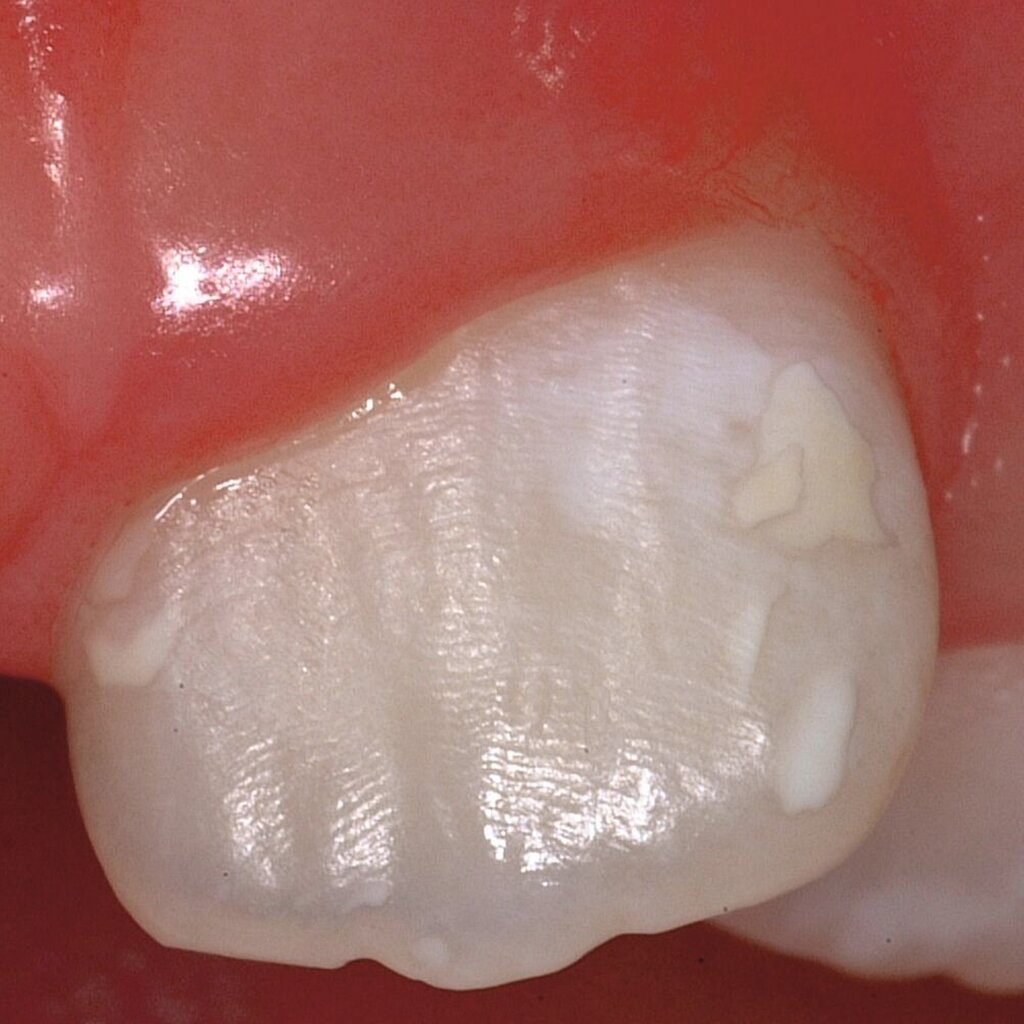

Bei post- beziehungsweise präeruptiven Oberflächendefekten ergibt sich in einigen Fällen die Indikation zur Restauration dieser MIH-Zähne. Unter Verweis auf die Lokalisation von MIH-bedingten Hypomineralisationen außerhalb der typischen Kariesprädilektionsstellen – zum Beispiel okklusale Fissuren und Grübchen oder Approximalflächen – werden diese als „atypische Restaurationen“ (engl.: „atypical restoration“, Abbildung 6) klassifiziert. Als ein weiteres Erkennungsmerkmal gilt die Präsenz von Hypomineralisationen im Bereich der Restaurationsränder. MIH- und kariesbedingte Restaurationen können und sollten sicher voneinander abgegrenzt werden.

Für die Dokumentation und Klassifikation der MIH wurden verschiedene Systeme vorgeschlagen. Als historisch und veraltet gilt der (modifizierte) DDE-Index. Demgegenüber haben die Kriterien der EAPD – abgegrenzte Opazitäten (Abbildung 3 und 4), Schmelzeinbrüche (Abbildung 5), atypische Restaurationen (Abbildung 6) – mittlerweile die weiteste Verbreitung gefunden. Diese wurden 2003 erstmals zur Beschreibung der MIH auf empirischer Basis publiziert [Weerheijm et al., 2003] und den Jahren 2010 und 2022 im Rahmen der damaligen MIH-Workshops bestätigt [Lygidakis et al., 2010; 2022].